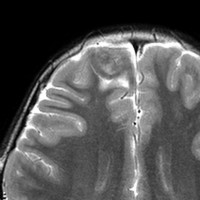

画像診断

- とても難しいといえます,特徴的な所見がないからです

- ほとんどが髄膜に接する脳表を巻き込む病変なのです

- 小さな多房性のう胞を伴ったり,脳内に結節とのう胞を形成するものもあります

- T1強調では等信号から低信号

- T2強調画像では低信号領域と血管のflow-voidがみられます

- ガドリニウム増強では不規則な増強像を見ることが多いです

- T2低信号の部分(結節)が強くガドリニウム増強されることも特徴かもしれません

難治性てんかんで発症した小児ですが,どう見てもDNTなのかなと思います。石灰化もありません。一般的に,meningioangiomatosisの術前診断は困難であると言えます。いずれにしても治療はlesionectomyです。